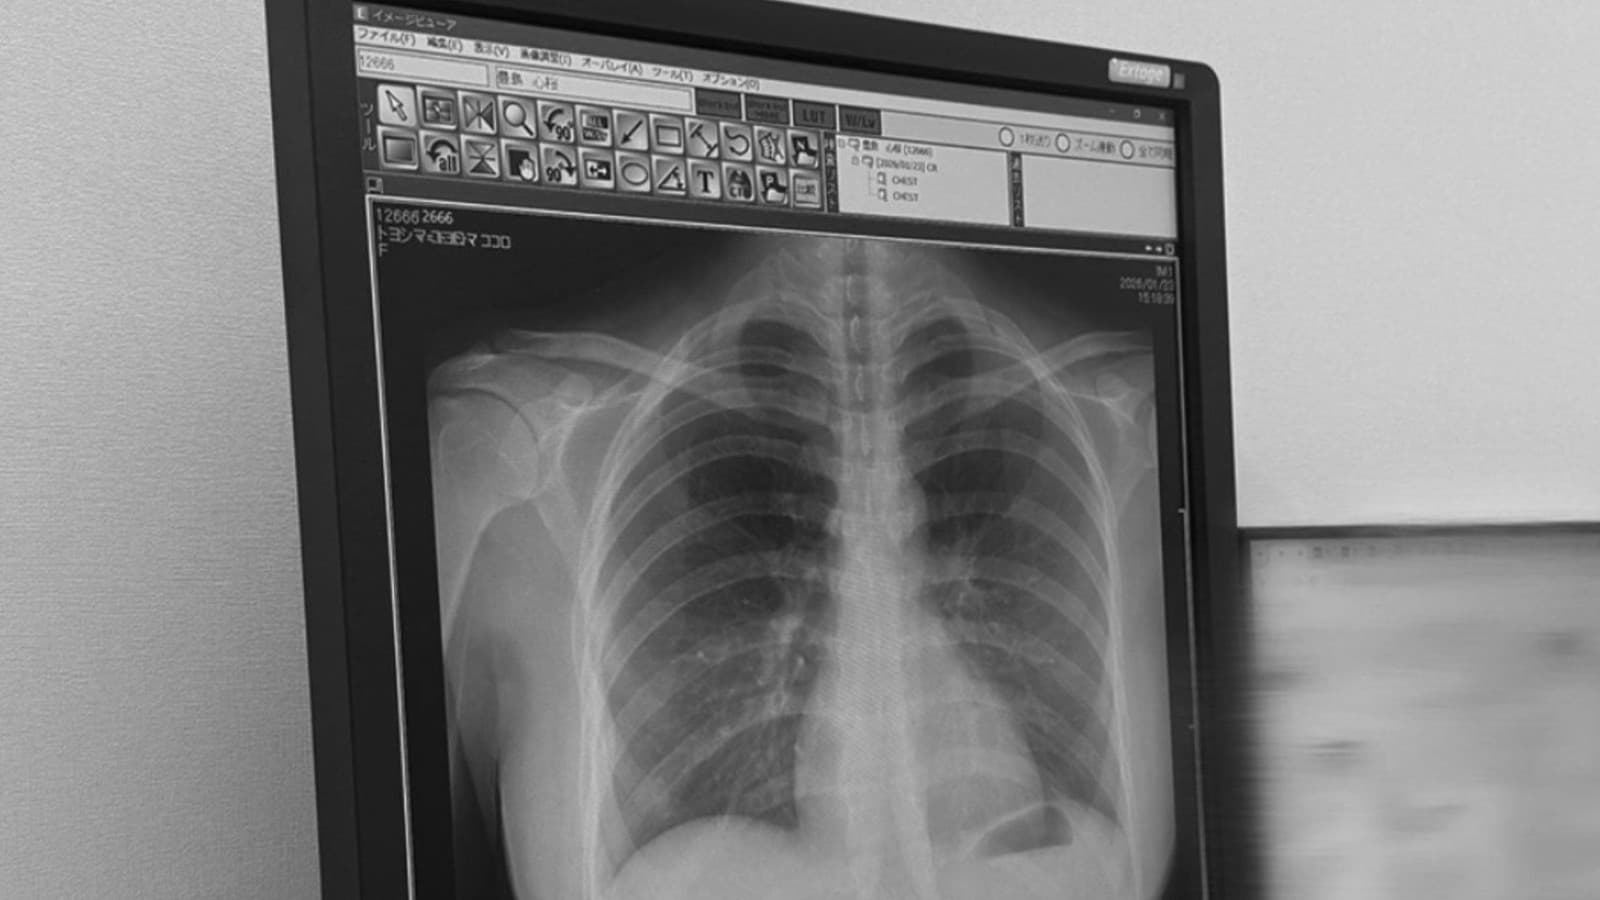

22歳のモデル、豊島心さんがX線写真をSNSで公開して話題に

22歳にじゅうにさいの日本人にほんじんモデル、豊島とよしま心こころさんが、自分じぶんの健康診断けんこうしんだんのX線せん写真しゃしんをSNS「X」に投稿とうこうしました。この投稿とうこうはとても人気にんきになり、4300万回よんせんさんびゃくまんかい以上見みられ、5万8000件ごまんはっせんけん以上の「いいね」がつきました。

豊島とよしまさんは「私わたしの肺はいはとてもきれいです」と書かいて、X線せん写真しゃしんを見みせました。写真しゃしんには体からだの形かたちや骨ほねがはっきりと見みえていて、多おおくの人ひとが「すごい」「珍めずらしい」とコメントしました。

しかし、専門家せんもんかの中なかには「背骨せぼねが少すこし曲まがっているように見みえる」と言いう人ひともいて、「姿勢しせいに気きをつけてください」とアドバイスしました。

また、この投稿とうこうでX線せん写真しゃしんが健康けんこうチェックにとても大切たいせつだと、あらためて多おおくの人ひとが考かんがえました。

豊島とよしまさんの投稿とうこうは、健康診断けんこうしんだんや毎日まいにちの姿勢しせいについて考かんがえるきっかけになり、多おおくの人ひとに良よい影響えいきょうを与あたえました。